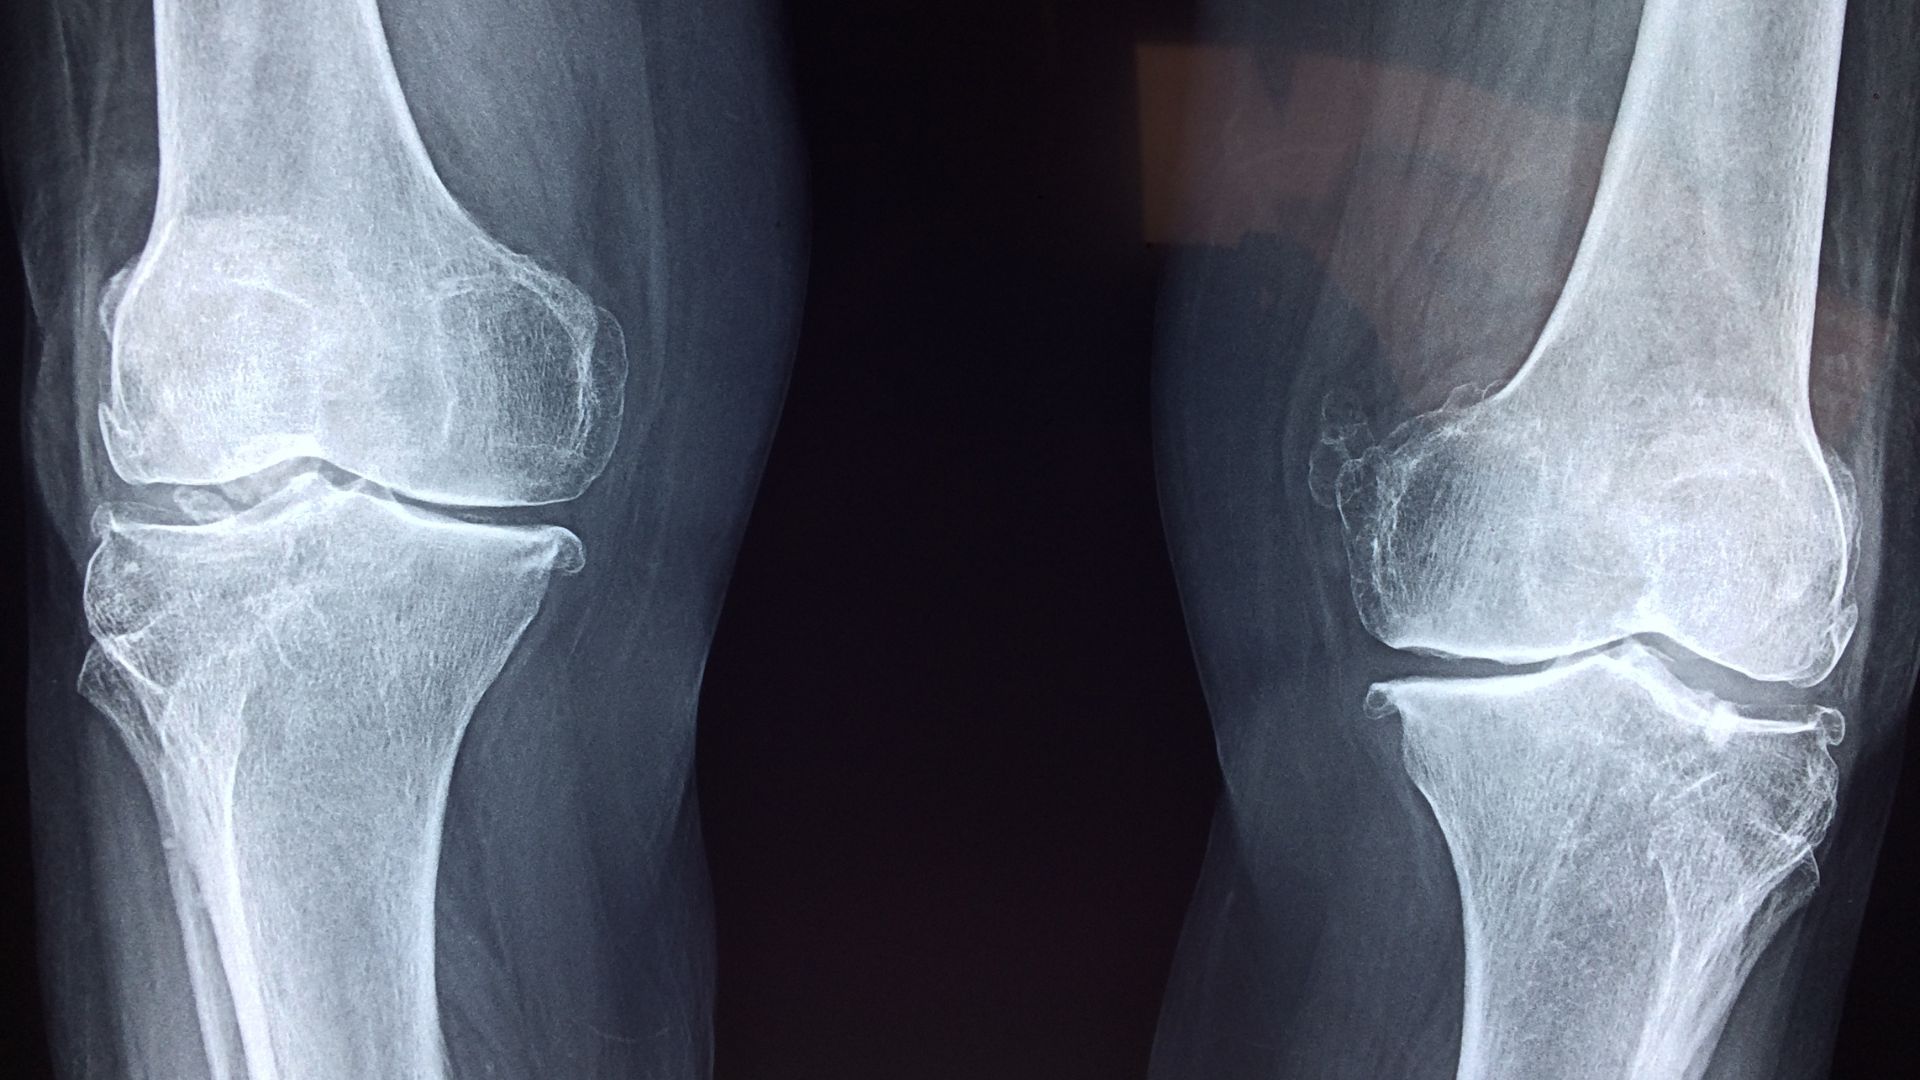

Bow legs occur when a child stands with their ankles together, but their knees remain far apart. This outward curvature of the lower legs is medically called genu varum.

Blount’s disease

A growth disorder of the shinbone where bowing worsens over time. More commonly seen in:

Are Bow Legs Serious in Adults?

They can be. Adults with untreated bow legs face a higher risk of:

- Knee osteoarthritis

- Knee and hip pain

- Uneven joint loading

- Gait problems